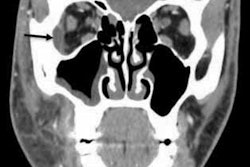

A CT of the mandible taken during that visit revealed an ossified soft-tissue mass of the right mandibular body containing teeth. Soft tissue was present along the surface of the bony area that extended caudally to the skin surface below the right side of the chin. No aggressive osseous features were revealed, and there was no evidence that injury or other stimuli formed new bone, the authors wrote.

A closer look revealed that the girl's mandibular alveolar ridge was widened by several millimeters on the left, and she couldn't depress her right lower lip. An MRI performed shortly after her birth showed an approximately 2.5 x 2 x 2-cm lesion arising from the right mandibular body. Several unerupted teeth also were detected, the authors noted.